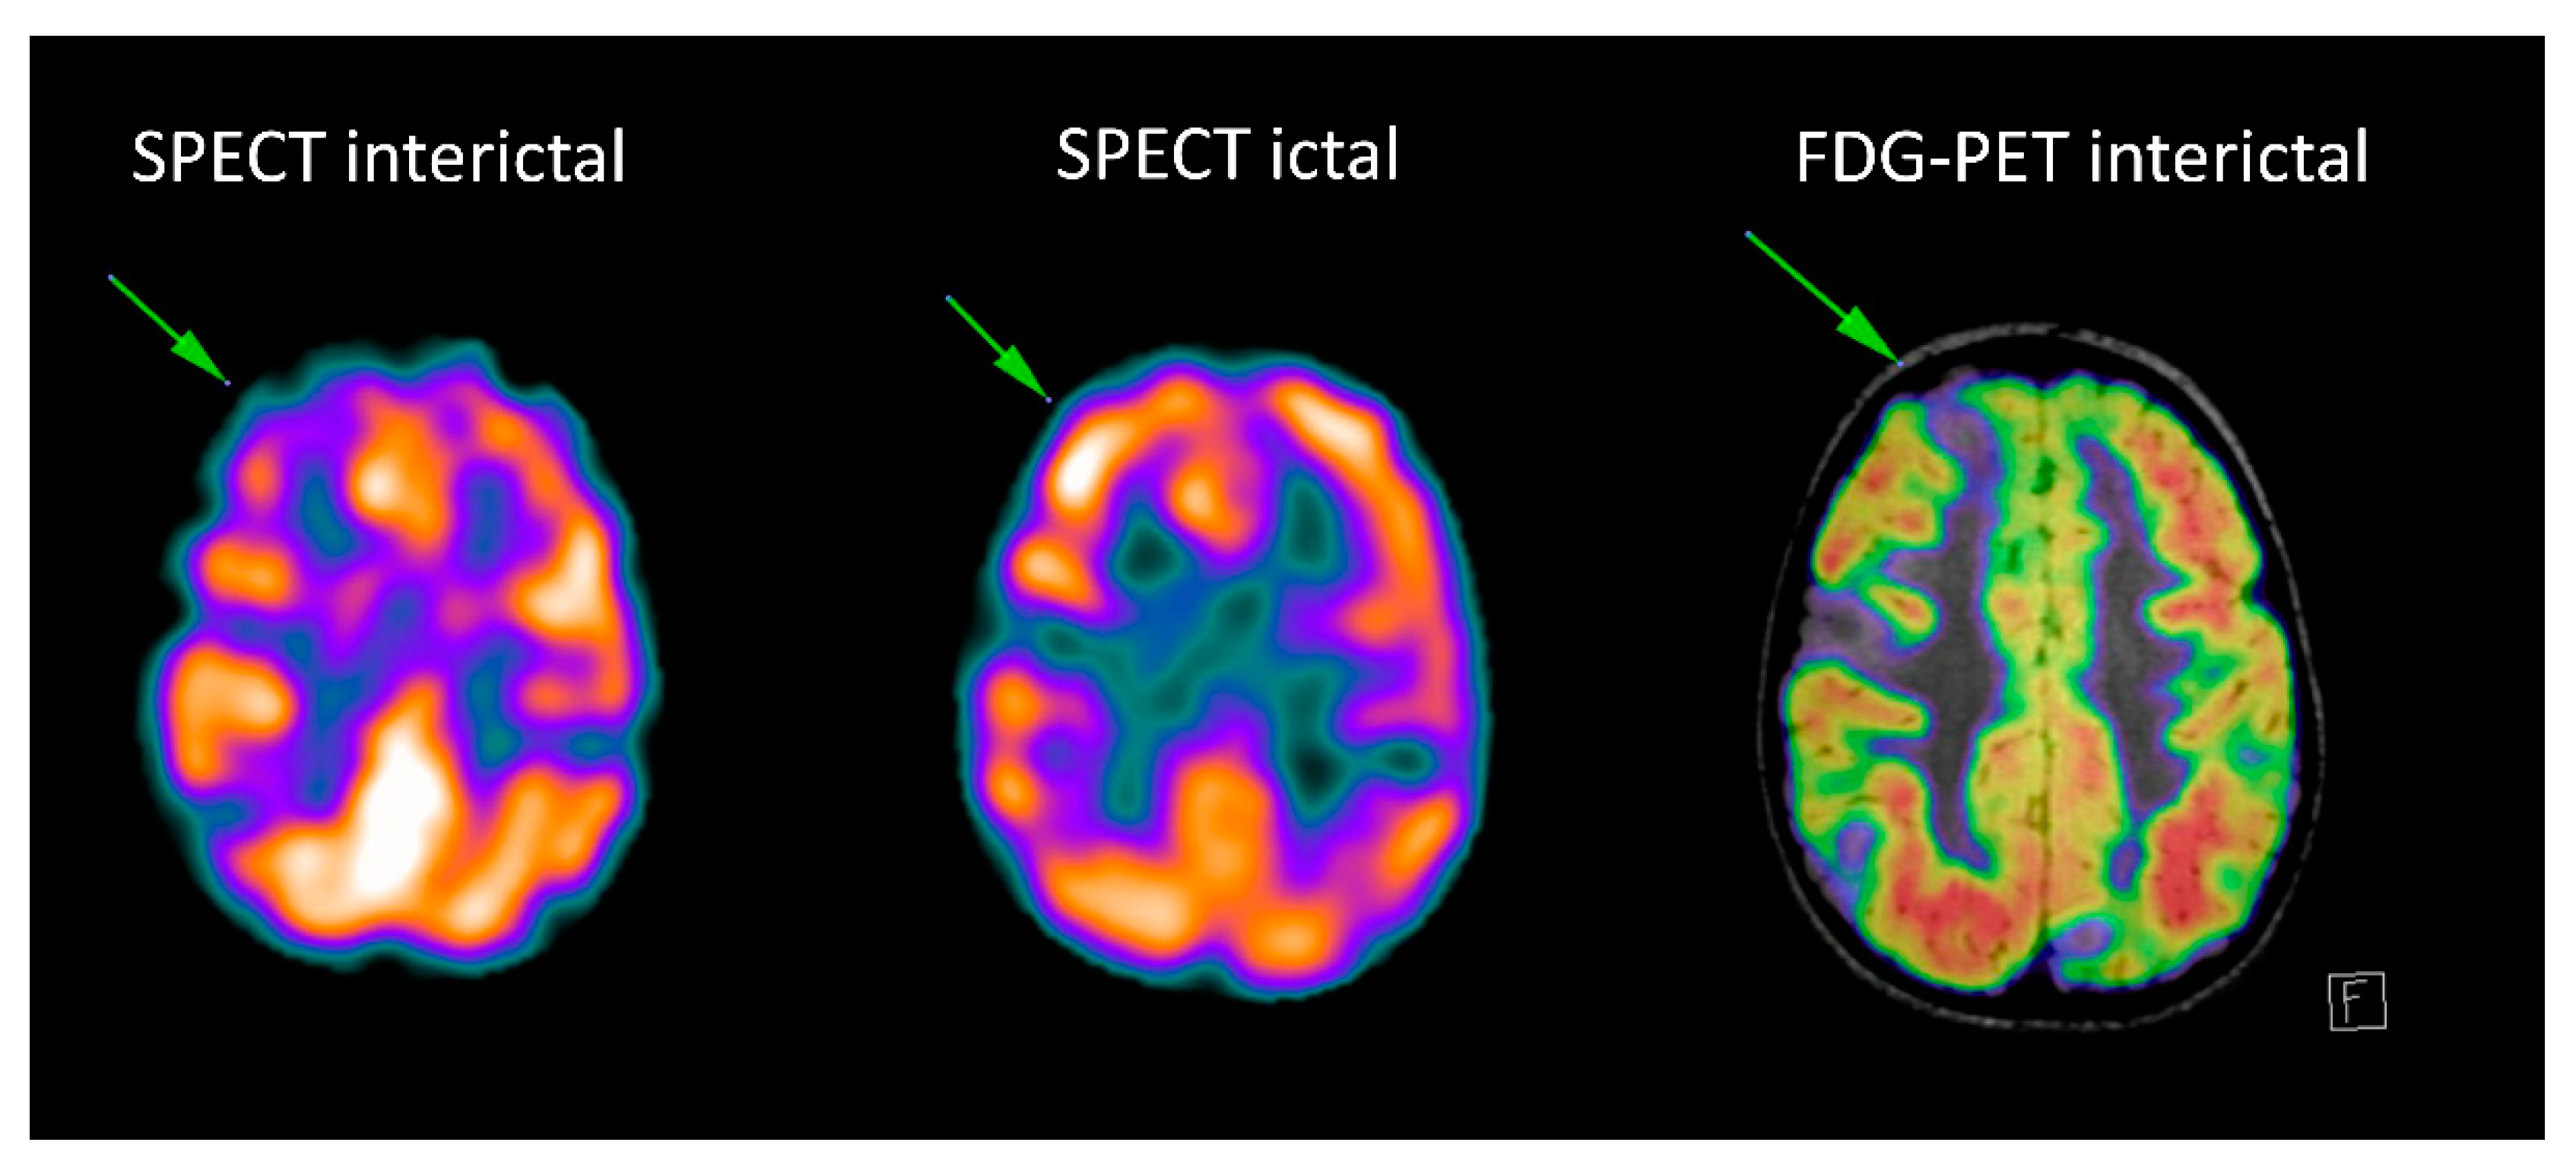

Figure 9.

Right frontal cavernoma. Axial CT image (a) shows right frontal periventricular hyperdensity (arrow) abutting the frontal horn of the lateral ventricle. Axial T2 (b), FLAIR (c), GRE (d) and DWI (e) trace images (b = 1000) show peripheral hypointense rim with central hyperintensity (arrow). Axial T1 VIBE post-contrast image (f) shows mild enhancement (arrow) consistent with cavernoma.